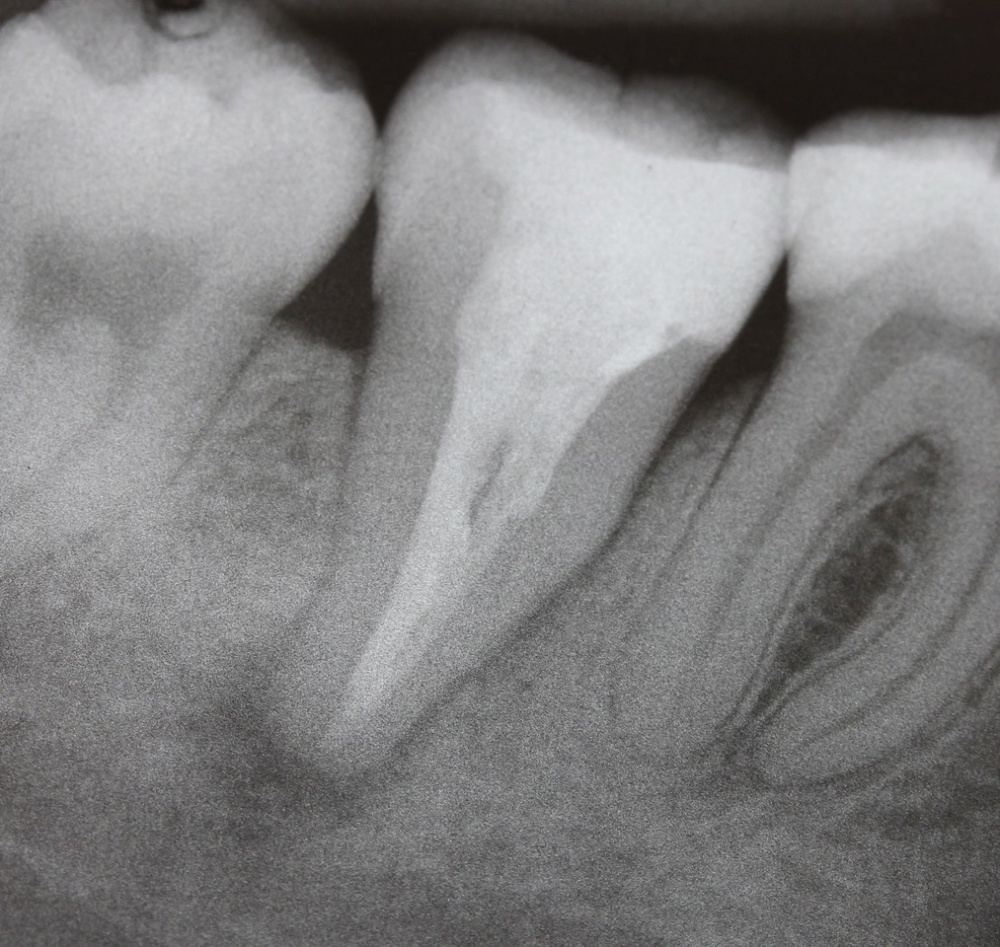

Im nächsten Fall stellte sich ein Patient mit reizunabhängigen Beschwerden und Perkussionsempflindlichkeit an Zahn 17 vor. Begleitend lag eine Lockerung Grad I bis II vor. Das daraufhin angefertigte Röntgenbild (Abb. 5) zeigt eine insuffiziente Wurzelfüllung, nebst Wurzelstift und einer umfangreichen apikalen Osteolyse. Darüber hinaus scheint Zahn 16 ebenfalls apikal beherdet zu sein und im Bereich der mesialen Wurzel besteht der Verdacht eines frakturierten Wurzelkanalinstrumentes.

Bei einem folgenden Kontrolltermin war der Patient weiterhin beschwerdefrei, es lag weder eine Schwellung noch ein Lockerungsgrad vor und auch die Perkussionsprobe verlief negativ. Das Kontrollröntgenbild 4 ½ Monate nach Insertion der Wurzelfüllung zeigt eine deutliche Regression der ehemals umfangreichen Osteolyse (Abb. 10). Im weiteren Verlauf der Behandlung ist die Entfernung des Instrumentenfragments aus dem mesiobukkalen Kanals des Zahnes 16 geplant, sowie die anschließende prothetische Neuversorgung der Zähne 16 und 17.